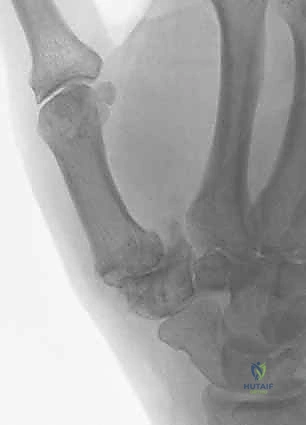

لماذا يتم استئصال العظم المربعي؟

المشكلة الأساسية في خشونة هذا المفصل هي احتكاك عظم المشط الأول (قاعدة الإبهام) بالعظم المربعي (Trapezium) بعد تآكل الغضروف بينهما. إزالة العظم المربعي بالكامل تقضي على هذا الاحتكاك، وبالتالي تقضي على مصدر الألم بشكل جذري.

ما هو التحدي بعد الاستئصال؟ ولماذا التعليق الوتري؟

إذا تم إزالة العظم المربعي فقط وترك الفراغ مكانه، فإن عظم المشط الأول للإبهام سوف ينزلق للأسفل (يهبط) باتجاه عظم القارب (Scaphoid) بسبب قوة الشد العضلي. هذا الهبوط يؤدي إلى قصر طول الإبهام، وضعف شديد في قوة القبضة، وقد يسبب ألمًا جديدًا نتيجة احتكاك المشطية بعظم القارب.

هنا يأتي دور العبقرية الجراحية في تقنية التعليق الوتري FCR. يتم استخدام جزء (شريحة) من وتر العضلة المثنية للرسغ الكعبرية (Flexor Carpi Radialis Tendon)، وهو وتر قريب ومتاح في المعصم ولن يؤثر أخذ جزء منه على وظيفة اليد. يتم استخدام هذا الوتر كـ "أرجوحة" أو "حبل تعليق" لربط قاعدة المشط الأول ومنعه من الهبوط في الفراغ الذي تركه العظم المربعي. الجزء المتبقي من الوتر يتم لفه ووضعه كـ "وسادة" (Interposition) داخل الفراغ لمنع احتكاك العظام.

![]()